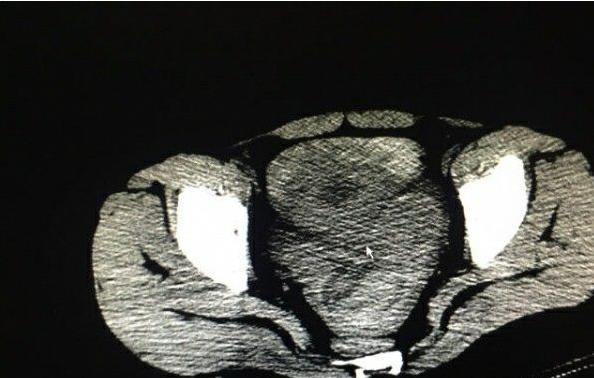

妇产科医生会诊,予以阴道后穹隆穿刺,留置导尿查尿妊娠试验后,基本确定患者:宫外孕破裂出血。立刻将患者送进了手术室,妇产科医生为她在腹腔镜下作了手术。整个手术过程很顺利,但是却从她的腹腔内吸引出多达2450ml的鲜血!正因为如此多的出血,才导致她在腹痛2个小时后便出现了休克的症状!